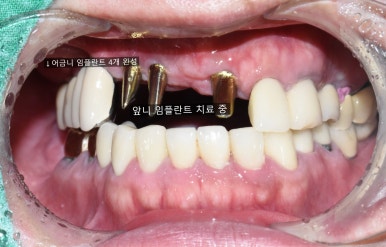

긴 브릿지가 흔들려서 임플란트를 하게 된 케이스

치료 전

어금니부터 일부 앞니까지 연결된 긴 브릿지가 흔들려서 임플란트를 하게 된 케이스

임플란트 완성

치료 후 사진: 일부 임플란트가 보이는 상태

앞니 브릿지가 흔들거리고 빠져요

처음 오셨을 때 상태

앞니 뿌리쪽까지 많이 썩어서 삭아 들어가서

앞니 브릿지가 붙을 곳이 없어서 흔들거리고 빠져서 온 상태입니다.

어금니쪽도 다른데서 한 임플란트가 찢어져서 임플란트 머리를 못 올린 상태였고

어금니도 몇 개 상실한 상태입니다.

치료전( 앞니 브릿지 떨어져서 덜렁이는 상태, 다른 곳에서 임플란트 찢어져 실패해서 잇몸에 묻혀진 상태)

어금니 타치과에서 실패한 인플란트(찢어져 있어서 임플란트 머리를 올리지 못한 상태)는 제거하고

어금니 빈 곳에 임플란트를 3개 심고 머리는 4개 만들어 어금니 4개 완성

및 앞니부위에는 기존 흔들리고 덜렁거리는 앞니 브릿지 제거하고

썩은 뿌리로 인한 염증치아의 썩은 뿌리만 남은 것 발치 후

앞니용 얇은 임플란트를 식립하였습니다.

네비게이션 임플란트를 사용하여 적절한 간격과 각도를 유지하였고

특히 앞니의 경우 뼈가 매우 얇았으나 내비게이션을 사용하여

뼈가 얇아도 뼈를 뚫고 나갈 위험이 없이 적절한 뼈 위치에 임플란트를 식립하였습니다.

어금니 임플란트 완성 및 임플란트 치료중 사진 (왼) / 완성 후 사진(오른쪽)

어금니 임플란트가 완성된 모습(왼쪽) 및 앞니 임플란트 진행중인 사진과

완성된 사진